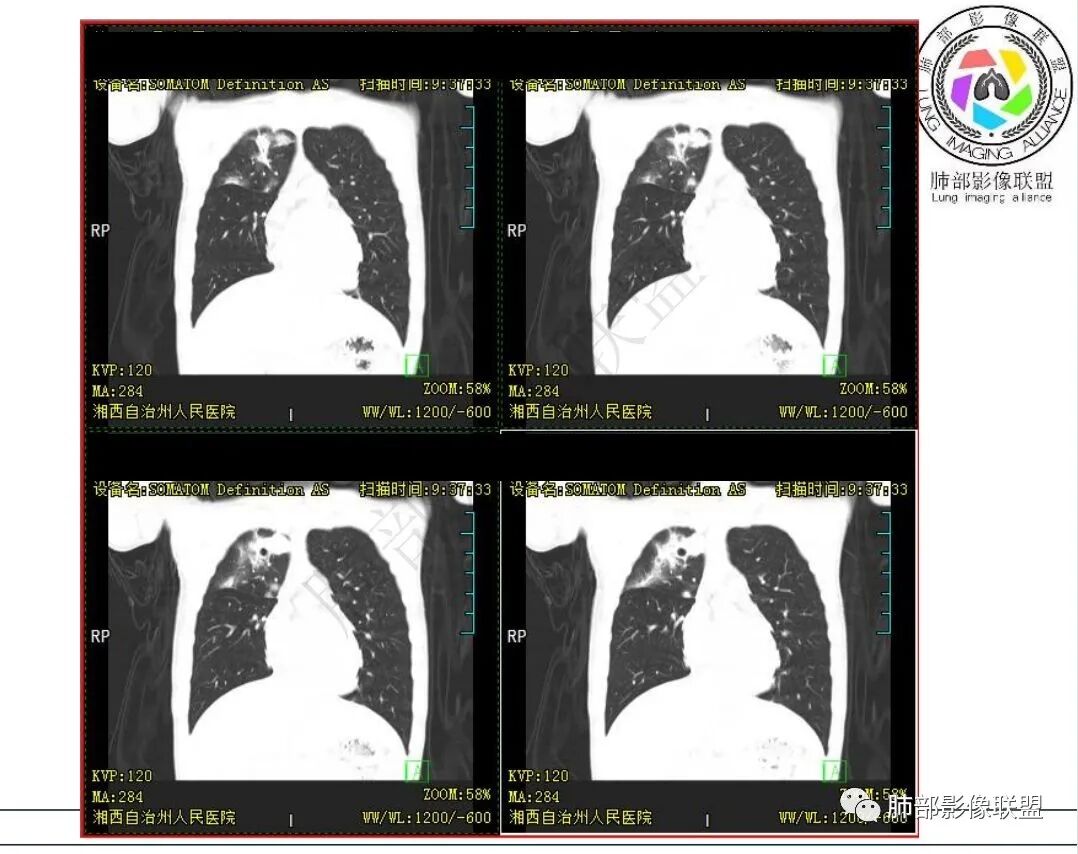

3.首次CT提示:右肺上叶多发结节影及实变影,簇状分布,周围散在磨玻璃影,结节内多类圆形空洞,内壁光整,有一定张力,偶见液平。部分支气管壁增厚。

4.患者年龄、临床与影像都会首先考虑结核,但是结核相关各项实验室检查均阴性,没有找到病原学依据。

因此,还应当排除NTM,影像可以酷似结核灶。

5.抛开分布不谈 其他的,临床中毒症状不明显、非易感人群,肺结节、实变、晕征、空洞等等都可以符合隐球感染。

本例病灶分布特点比较偏中央分布,不是我们常见的隐球外围胸膜下。看来诊断隐球,分布不能太绝对,至少不能作为绝对排除项。